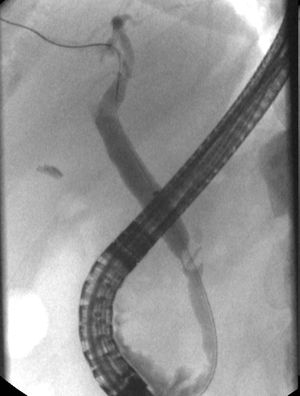

69-year old female presented with a monthlong abdominal pain and nausea with vomiting. Initial workup showed mild increase of aminotransferases (AST, 64.8U/L; ALT, 99.6U/L). Ultrasound was unremarkable. Few days later aminotransferases increased (AST, 1652U/L; ALT, 1785U/L), with elevated total bilirubin (1.7mg/dL), CRP (47mg/L) and leukocytosis. Her medical history was notable for laparoscopic cholecystectomy 17 years earlier during which cystic duct and artery were ligated. During current work up patient underwent endoscopic ultrasound that showed 11mm gallstone in the bile duct. At subsequent ERCP a 10mm×6mm suspected stone with a central oval radiopaque defect (Fig. 1) in the common hepatic duct at the level of cystic duct was successfully extracted. Surgical clip within the stone was identified (Fig. 2).